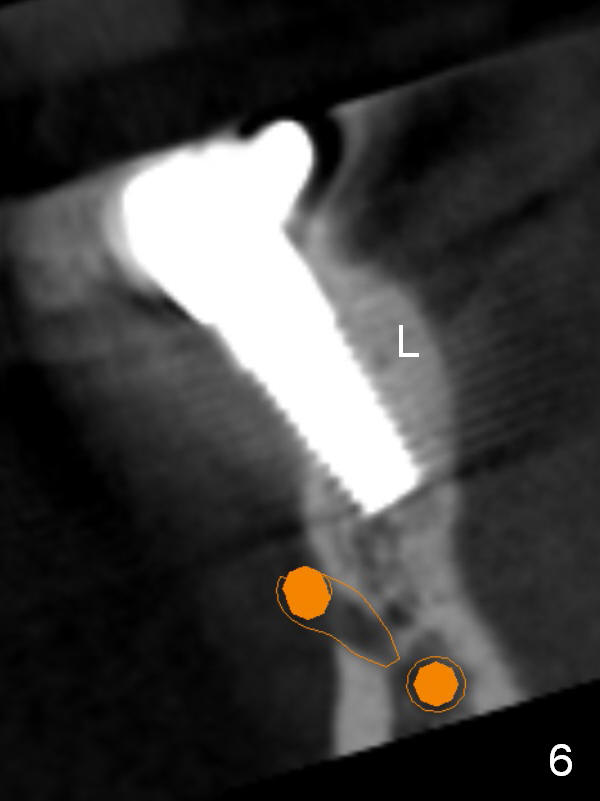

CBCT confirms buccal malpositioning (Fig.6, coronal section at #29). It can be corrected immediately (Fig.7,8). It appears that the latter correction is more appropriate. After implant removal, the buccal aspect of the lingual plate is removed (Fig.9 red area) before starting a new osteotomy site and deepening it (brown line).